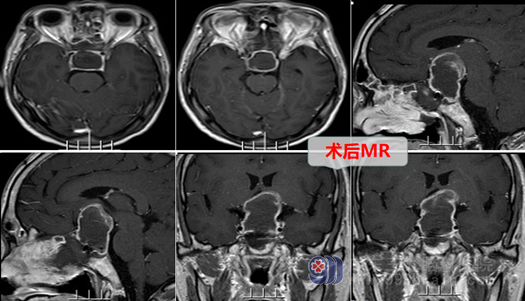

陈先生欣然的接受了这个方案,在完善准备后,接受了外十科团队为其行经鼻蝶鞍区占位切除术,垂体肿瘤被完全切除了,视神经、视交叉的眼解除了,陈先生的视力也得到了一定的恢复。